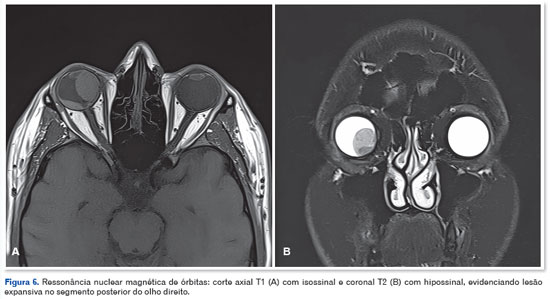

A ressonância magnética de órbitas confirmou uma lesão expansiva no segmento posterior do OD, com isossinal em T1 e hipossinal em T2, sem infiltração extraocular visível (Figura 6). Exames sistêmicos e laboratoriais descartaram metástases ou anormalidades sistêmicas. Devido à rápida progressão da lesão e ausência de prognóstico visual, optou-se pela enucleação do OD.

O diagnóstico diferencial é um desafio, envolvendo outras massas do corpo ciliar, como melanomas, nevus, adenomas e adenocarcinomas epiteliais1. No caso relatado, a ultrassonografia ocular e a ressonância magnética foram fundamentais para caracterizar a extensão e a localização da lesão. As características imagiológicas, como ausência de ângulo kappa na ultrassonografia e isossinal em T1 na ressonância, não eram típicas de melanoma. Contudo, devido ao rápido crescimento, comprometimento visual severo e ausência de alternativas terapêuticas eficazes, optou-se pela enucleação.